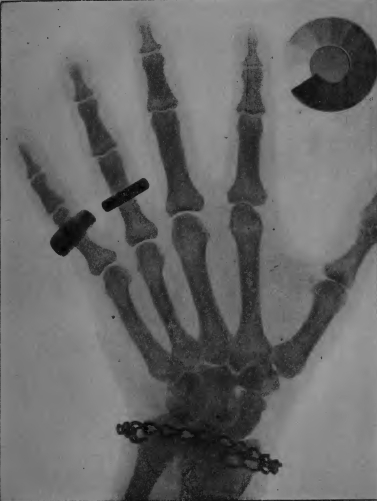

Planche II. — Radiographie d'une main (positif). A l'annulaire une bague d'or très opaque aux rayons X. Au petit doigt une bague d'aluminium bien moins opaque: l'ombre de l'os s'aperçoit au travers de cette bague. Au poignet un bracelet de fer avec une plaque d'aluminium mince, peu visible sur la radiographie en raison de sa transparence. Les os, bien moins opaques que les bagues, donnent cependant des ombres très nettes laissant voir des détails de structure. Le contour des chairs se voit faiblement. A côté de la main se trouve un radiochromomètre radiographié en même temps que celle-ci. Il indique une dureté de rayons de 6e Benoist.

[3] On emploie couramment, pour reconnaître la dureté des rayons, un petit appareil très simple nommé radiochromomètre Benoît. Le principe de l'appareil consiste à comparer la transparence aux rayons X d'une mince lame d'argent à la transparence d'une série de secteurs d'aluminium d'épaisseurs graduées. Pour se servir du radiochromomètre on peut examiner l'ombre qu'il porte sur un écran radioscopique ou bien reproduire son image en radiographie comme sur la planche 3. L'aspect de l'image permet d'apprécier la dureté des rayons employés.